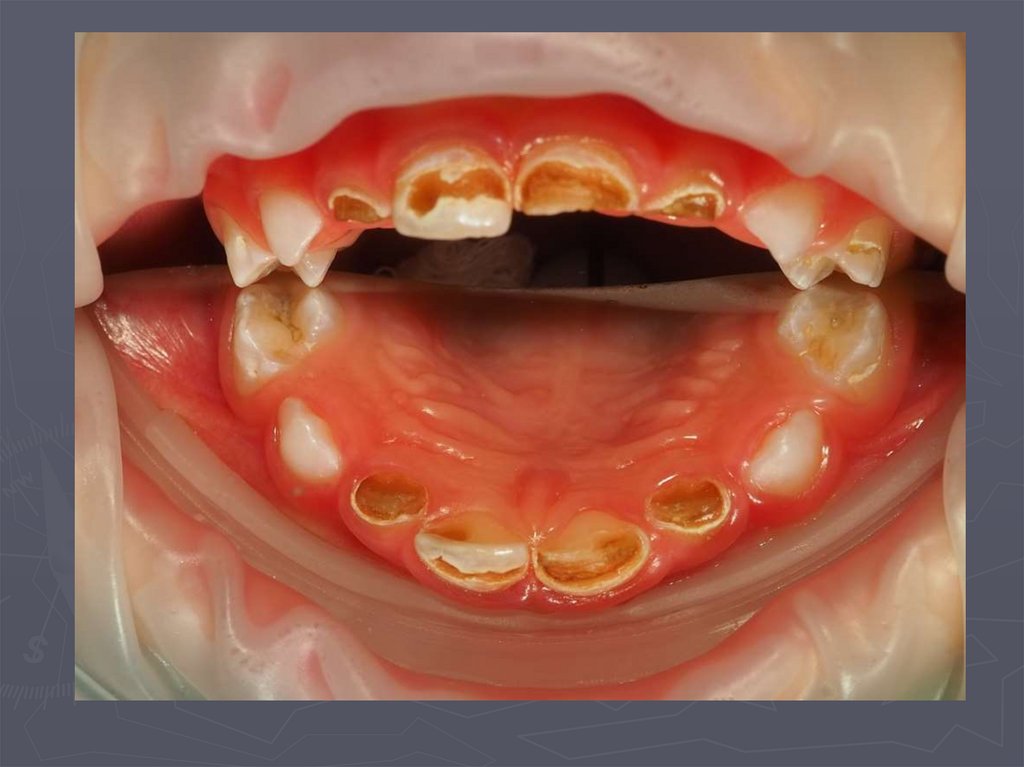

Циркулярный кариес

4. ОСОБЕННОСТИ КЛИНИЧЕСКОГО ПРОЯВЛЕНИЯ КАРИЕСА У ДЕТЕЙ РАННЕГО ВОЗРАСТА

У детей в возрасте от 1года до 3 лет КАРИЕС

чаще возникает:

► на зубах, имеющих порочно развитые ткани в виде

гипоплазии;

► ткани этих зубов недостаточно минерализованы;

► чаще поражаются резцы;

► затем моляры и клыки;

► преимущественная локализация кариозной полости на

вестибулярной и контактной поверхности резцов ;

► а также в фиссурах моляров;

► нередко кариес начинается в пришеечной области;

► процесс распространяется вокруг всей коронки;

► формируется циркулярный кариес.

8. Циркулярный кариес